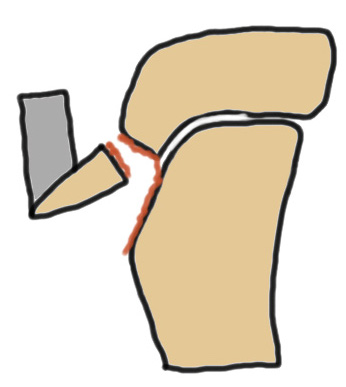

Mechanism

Forceful eccentric contracture of the quadriceps

- initiating a jump or landing

- knee flexed

Type III

Technique

Restore articular surface